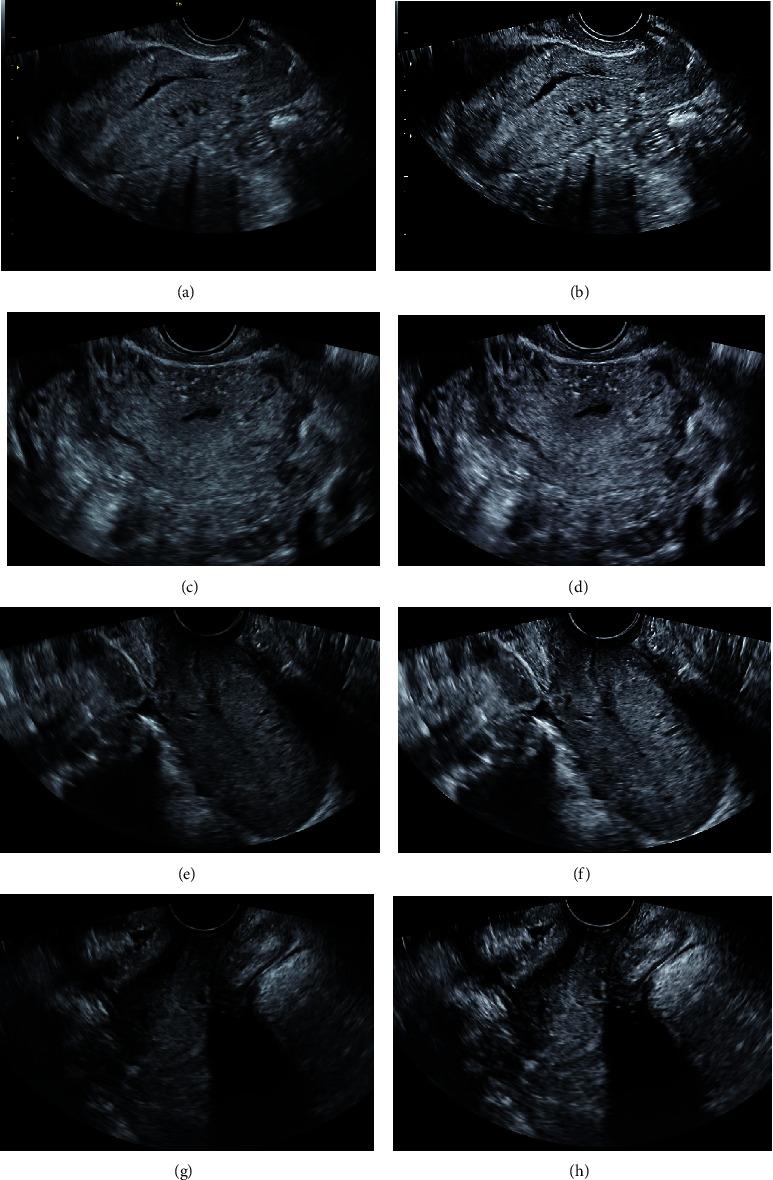

In order to explore the application value of image enhancement algorithm in evaluating pelvic floor rehabilitation training in the prevention of postpartum female pelvic floor dysfunction (FPFD), 70 patients with FPFD were selected as the study subjects and randomly divided into two groups. One group received routine nursing (control group, = 35), and the other group received pelvic floor rehabilitation training based on routine nursing (experimental group, = 35). In ultrasound images based on an image enhancement algorithm, the International Consultation on Incontinence Questionnaire-Short Form (ICIQ-SF), and Pelvic Floor Distress Inventory-20 (PFDI-20) were used to evaluate the efficacy. The results showed that after image enhancement algorithm processing, the image signal-to-noise ratio (SNR), peak signal-to-noise ratio (PSNR), and structural similarity index (SSIM) of ultrasound images of patients with FPFD were significantly improved ( < 0.05); the mean square error (MSE) was significantly decreased ( < 0.05); the diagnostic accuracy of FPFD in the original ultrasound images was 73.34%, and that after image enhancement algorithm processing was significantly improved to be 89.86% ( < 0.05). In addition, the overall clinical response rate of FPFD in the experimental group (82.86%) was obviously higher than that in the control group (51.43%) ( < 0.05). After rehabilitation training, the ICIQ-SF and PFDI-20 scores of patients with FPFD in the two groups suggested a significant decrease ( < 0.05). In summary, using an image enhancement algorithm has a good application prospect in evaluating pelvic floor rehabilitation training in preventing postpartum FPFD and is worthy of further promotion.

为了探讨图像增强算法在评估盆底康复训练预防产后女性盆底功能障碍(FPFD)中的应用价值,选取 70 例 FPFD 患者作为研究对象,随机分为两组。一组接受常规护理(对照组,n=35),另一组在常规护理基础上接受盆底康复训练(实验组,n=35)。在基于图像增强算法的超声图像、国际尿失禁咨询问卷-简短表(ICIQ-SF)和盆底疾病困扰问卷-20 项(PFDI-20)中评估疗效。结果显示,经过图像增强算法处理后,FPFD 患者的超声图像的信噪比(SNR)、峰值信噪比(PSNR)和结构相似性指数(SSIM)均明显提高( < 0.05);均方误差(MSE)明显降低( < 0.05);原始超声图像对 FPFD 的诊断准确率为 73.34%,经图像增强算法处理后明显提高至 89.86%( < 0.05)。此外,实验组 FPFD 的整体临床总有效率(82.86%)明显高于对照组(51.43%)( < 0.05)。康复训练后,两组 FPFD 患者的 ICIQ-SF 和 PFDI-20 评分均明显下降( < 0.05)。综上所述,图像增强算法在评估盆底康复训练预防产后 FPFD 中具有良好的应用前景,值得进一步推广。